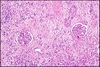

2

3

Q

What are the differences seen in an otherwise stereotypical inflammatory reaction?